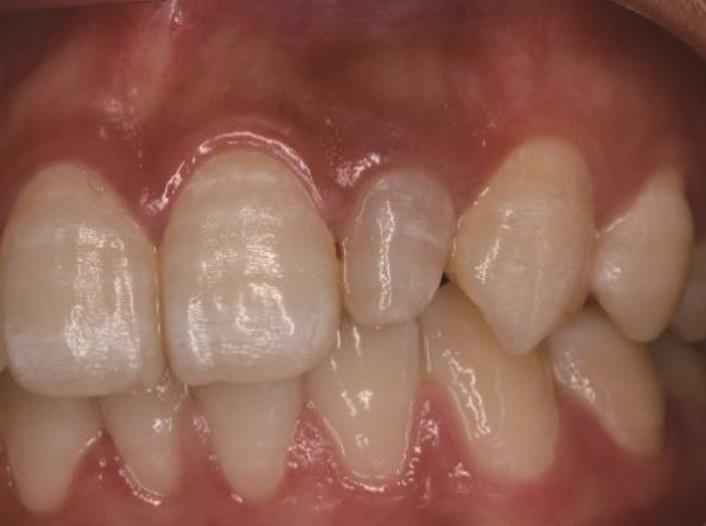

• 显微根尖手术治疗上颌侧切牙Oehlers Ⅲ型牙内陷1例

2024, 49(1):101-104. DOI: 10.13406/j.cnki.cyxb.003375

摘要 (34) HTML (13) PDF 9.96 M (122) 评论 (0) 收藏

摘要: